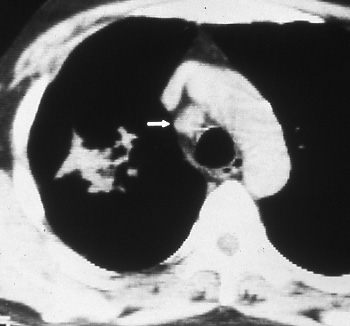

Fig. 25a & b: a) Posterior-anterior chest radiograph shows a mass with irregular borders and infiltrate in the right upper lobe. b) Computed tomographic scan of the chest delineates the right upper lobe mass and enlarged lower paratracheal nodes (white arrow), N2 disease.